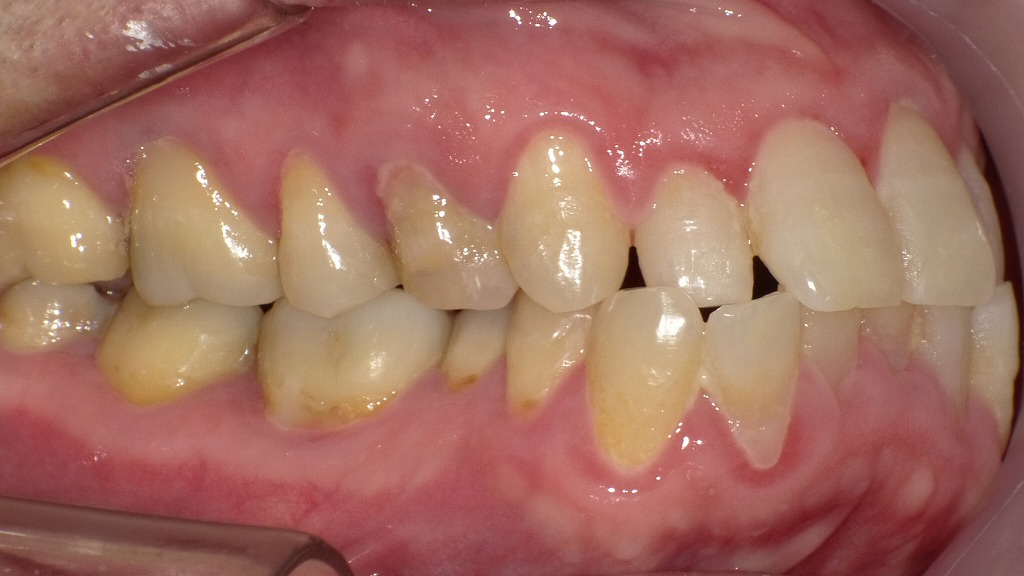

磨き残しが炎症を引き起こした症例

前歯から奥歯の歯肉にかけて赤み・腫れがみられ、歯肉炎の典型的な所見を示しています。歯と歯ぐきの境目に付着したプラーク(歯垢)が炎症の主な原因で、適切に除去されないと出血・腫脹・発赤が進行します。毎日の丁寧なブラッシングと定期的なクリーニングが、健康な歯ぐきを保つために重要です。

🔸【上顎3番~6番に顕著な出血が見られる歯肉炎の症例】

🦷【症状1】上顎犬歯から第1大臼歯にかけての出血

- **上顎3番(犬歯)〜6番(第一大臼歯)**にかけて、顕著な歯ぐきからの出血が確認されます。

- 広範囲にわたる歯肉炎の進行が疑われるケースです。

🪥【症状2】歯列不正によるブラッシング不足

- 歯並びが不正なため、歯ブラシが届きにくく、プラークが大量に残存しています。

- 清掃不良が慢性的な炎症の引き金となっていると考えられます。

😷【症状3】歯ぐきの腫れ・自然出血・仮性ポケット形成

- 歯ぐきは赤く腫れあがり、自然に出血している状態です。

- 仮性ポケットが形成されており、指で触れると歯ぐきが「ペロン」とめくれるのが特徴です。

- 炎症によって歯周組織が一時的に離開している状態であり、歯周病への進行リスクがあります。